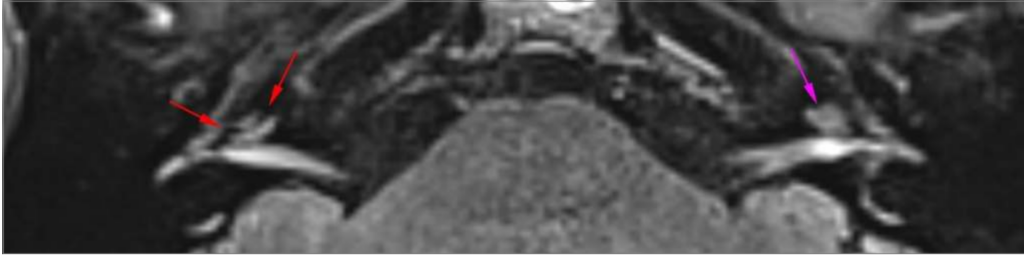

Não há sinais de hidropsia cocleovestibular à esquerda (setas roxas).

Há obliteração completa do vestíbulo à direita (hidropsia vestibular acentuada grau III – seta verde). Destaca-se, ainda, extensão da alteração do sinal relacionada à hidropsia ao canal semicircular lateral junto à confluência com o vestíbulo deste lado (seta amarela), sendo

que o mesmo, assim como todo o labirinto membranoso, tem sinal preservado na sequência fortemente ponderada em T2 o que indica que estão pérvios.

Observa-se, também, alargamento do espaço endolinfático coclear à direita, com obliteração parcial e irregular da scala vestibuli (hidropsia coclear grau I de Baráth – seta vermelha).

Comentário: Chama a atenção o grau acentuado de hidropsia endolinfática no lado direito que aparentemente se estende ao canal lateral do mesmo lado.